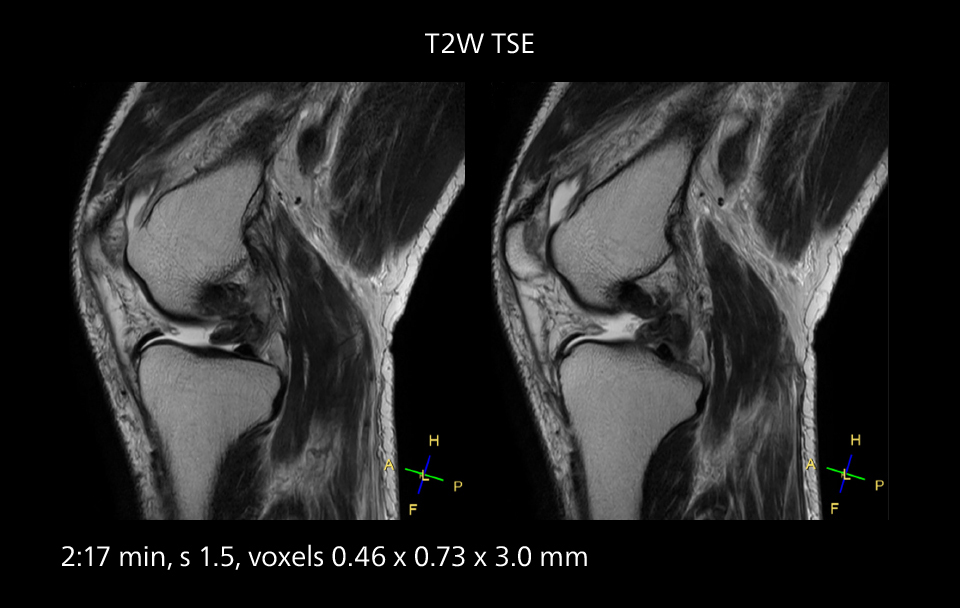

MRI of the knee

Images showing a posterior cruciate ligament (PCL) tear, a detached medial collateral ligament (MCL) on the tibial side and an intact anterior cruciate ligament (ACL). SmartPath to Elition X helped reduce scan time compared to previous imaging while maintaining resolution.

An example of increased imaging speed is in knee studies. “There is a definite scan time reduction for T2* mFFE and proton density TSE – both of these sequences benefit from much shorter repetition times,” he reports.

Overall, imaging time per sequence has been reduced since the Elition X upgrade. This can help reduce the risk of patient movement and the need for rescans.